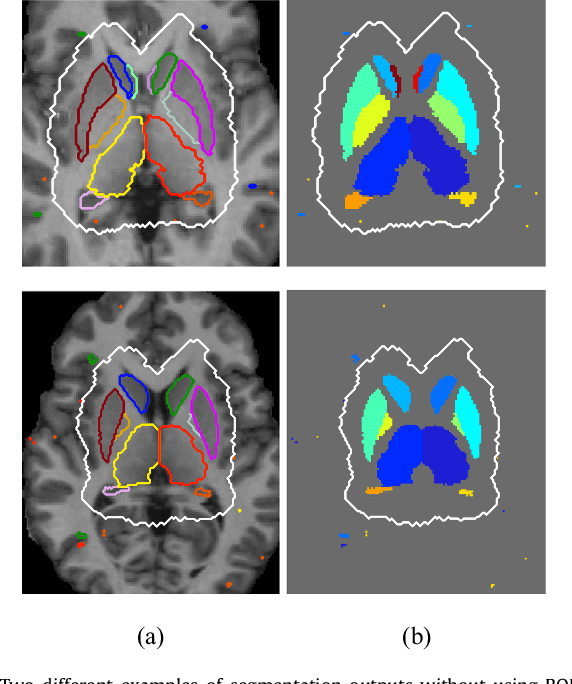

Abstract:Sub-cortical brain structure segmentation in Magnetic Resonance Images (MRI) has attracted the interest of the research community for a long time because morphological changes in these structures are related to different neurodegenerative disorders. However, manual segmentation of these structures can be tedious and prone to variability, highlighting the need for robust automated segmentation methods. In this paper, we present a novel convolutional neural network based approach for accurate segmentation of the sub-cortical brain structures that combines both convolutional and prior spatial features for improving the segmentation accuracy. In order to increase the accuracy of the automated segmentation, we propose to train the network using a restricted sample selection to force the network to learn the most difficult parts of the structures. We evaluate the accuracy of the proposed method on the public MICCAI 2012 challenge and IBSR 18 datasets, comparing it with different available state-of-the-art methods and other recently proposed deep learning approaches. On the MICCAI 2012 dataset, our method shows an excellent performance comparable to the best challenge participant strategy, while performing significantly better than state-of-the-art techniques such as FreeSurfer and FIRST. On the IBSR 18 dataset, our method also exhibits a significant increase in the performance with respect to not only FreeSurfer and FIRST, but also comparable or better results than other recent deep learning approaches. Moreover, our experiments show that both the addition of the spatial priors and the restricted sampling strategy have a significant effect on the accuracy of the proposed method. In order to encourage the reproducibility and the use of the proposed method, a public version of our approach is available to download for the neuroimaging community.